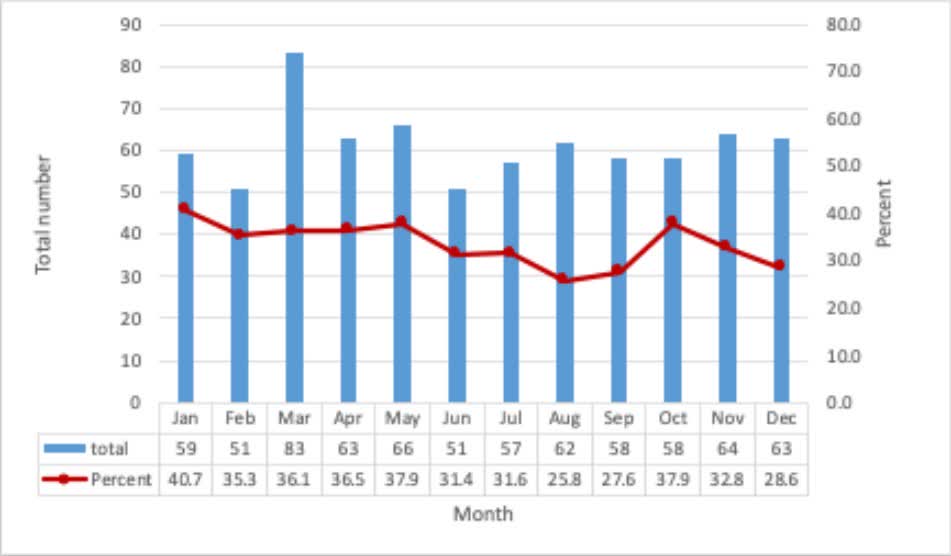

Antecedent Flu-Like Illness and Onset of Idiopathic Dilated Cardiomyopathy: The DCM Precision Medicine Study W. H. Wilson Tang, MD Mark Drazner Anjali Owens Palak Shah Daniel D. Kinnamon, PhD @markhofmeyer Jane Wilcox, MD, MSc Elizabeth Jordan #AHAJournals ahajrnls.org/4lAS6Ln